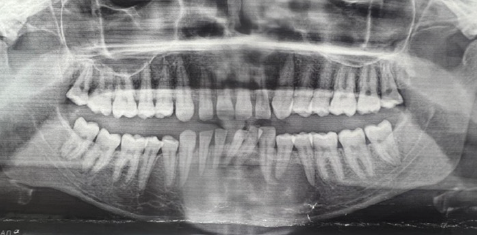

The patient’s chief concern was the rapid rate of growth and the sudden onset of tooth mobility. A panoramic radiograph, provided by the patient, revealed a radiolucent area extending occlusogingivally from just below the alveolar crest to the inferior border of the mandible, mediolaterally from tooth 35 crossing the midline to tooth 43, causing lateral displacement of the lower incisors (Figure 2). A chairside aspiration of the lesion was performed to determine the nature of the swelling, which turned out to be mostly negative with few drops of blood.

Figure 2. 2D Panoramic radiograph showing well defined radiolucency at the area of the lower anterior teeth.